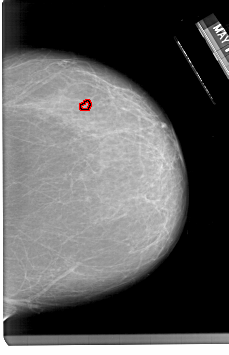

A_1333_1.LEFT_CC

RIGHT_CC LINES 6736 PIXELS_PER_LINE 4336 BITS_PER_PIXEL 12 RESOLUTION 43.5 OVERLAY

FILE: A_1333_1.RIGHT_CC.OVERLAY

TOTAL_ABNORMALITIES 1

ABNORMALITY 1

LESION_TYPE CALCIFICATION TYPE PLEOMORPHIC DISTRIBUTION CLUSTERED

ASSESSMENT 4

SUBTLETY 2

PATHOLOGY BENIGN

TOTAL_OUTLINES 1

BOUNDARY